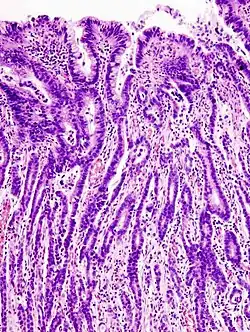

Histopatologia

Rak żołądka może występować w różnych postaciach, jako: gruczolakorak, rak jelitowy lub rozlany, może tworzyć przerzuty[8]. Rak żołądka u ssaków domowych i gospodarskich jest klasyfikowany jak u ludzi, według klasyfikacji WHO, choć niektórzy proponują pewne modyfikacje tego systemu. Rzadko klasyfikuje się nowotwór według klasyfikacji Lauréna[9]. Zwykle dominującym podtypem histopatologicznym jest gruczolakorak, jednak u koni jest to rak płaskonabłonkowy[6]. U kotów najczęstszym złośliwym nowotworem nabłonkowym jest gruczolakorak i rak niezróżnicowany[6][10].